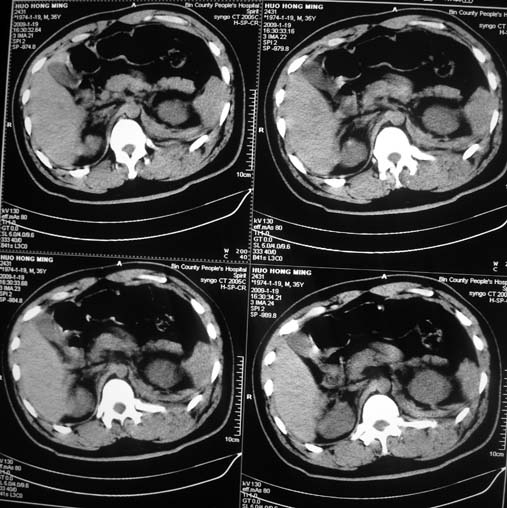

以下是引用余辉在2009-1-20 8:22:00的发言:[br]右侧肾上腺明显增大、边缘不光整,肯定有问题,结合患者病史考虑肾上腺挫伤、伴血肿形成。[br]另左肾后唇包膜下方可见局限性新月形高密度影,考虑肾包膜下出血[br]余同意楼上,建议增强排除脾破列

以下是引用随光逐影在2009-1-20 8:21:00的发言:[br]1)左侧多发肋骨及部分腰椎左侧横突骨折。2)左侧肾旁后间隙及同侧胸腔积血。3)左侧腰大肌肿胀。